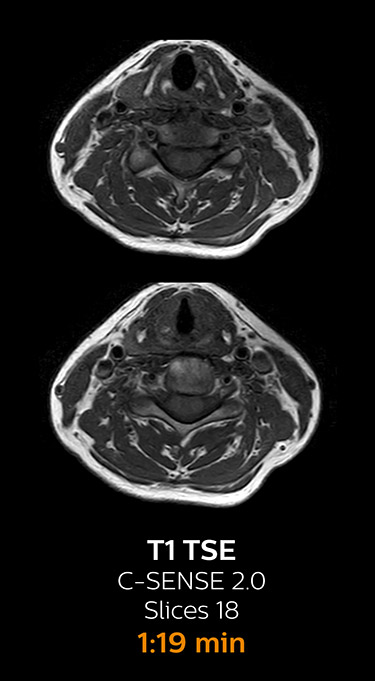

which corresponds to 34% reduction.

With Compressed SENSE, the scan time for the routine lumbar spine examination at KNC was reduced from 11:41 to 8:17 minutes,

MRI examination of the lumbar spine with Compressed SENSE

Ingenia 3.0T CX

Scan time 8:17 min. (was 11:41 min. without Compressed SENSE)